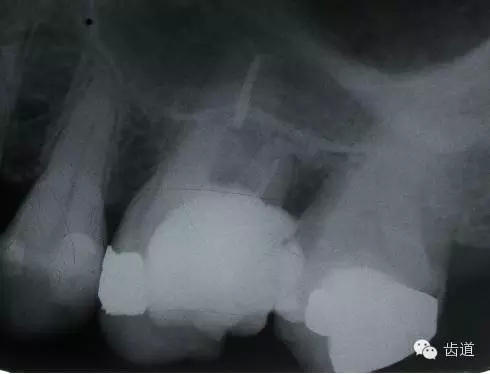

左下7根充后下唇麻木

左下5根管預(yù)備后下唇麻木